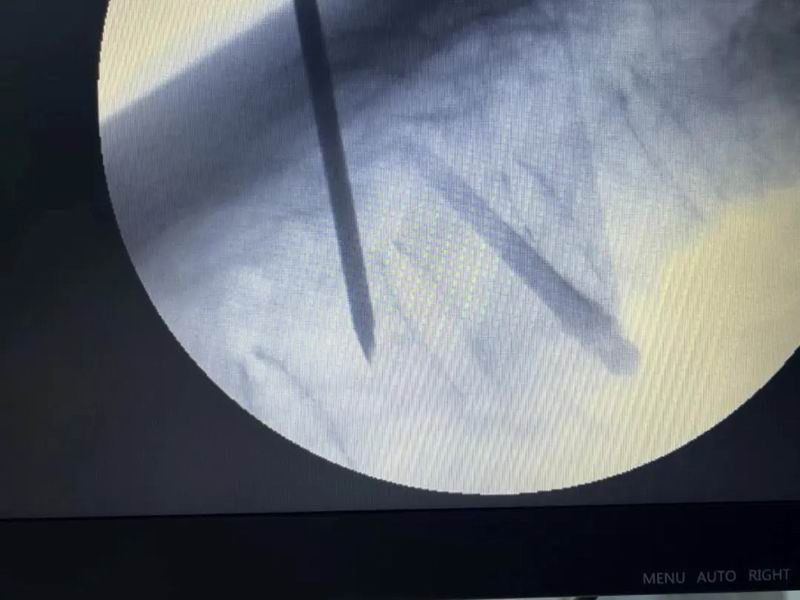

在精确的C臂引导下,骨科专家郭伯英与许主任携手并进,他们运用精湛的技术,通过特制的穿刺针精准地穿入患者椎体。随着默契的配合,骨水泥被准确无误地注入病变的椎体中。透视结果显示,骨水泥分布均匀,未见周边泄漏,标志着这次手术取得圆满成功。